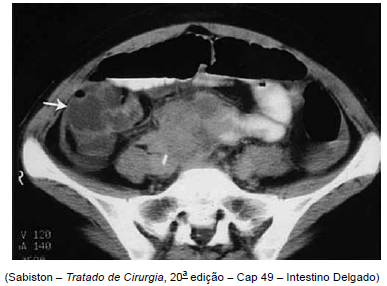

Homem de 20 anos deu entrada no Pronto-Socorro apresentando, há 4 dias, febre alta, diarreia, distensão e dor abdominal difusa de forte intensidade, com vários episódios de vômitos. Nega cirurgias prévias. Realizada tomografia abdominal de abdome demonstrada a seguir.

O diagnóstico do paciente é: